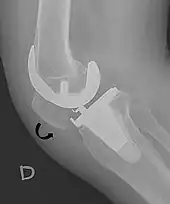

- ↑ Melloni, Pietro; Veintemillas, Maite; Marin, Anna; Valls, Rafael (2013). "Imaging Patellar Complications After Knee Arthroplasty". Arthroplasty - Update. doi:10.5772/53666. ISBN 978-953-51-0995-2. (CC-BY-3.0)

- 1 2 Douglas Dennis (2017-02-25). "TKA in Patella Baja (Infera)". Orthobullets. Retrieved 2019-02-08.